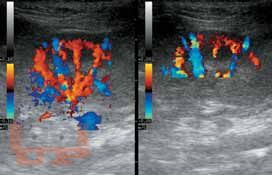

Книга восполняет острый дефицит в учебной литературе по УЗИ мелких домашних животных (кошек и собак). В ней систематизированы и стандартизированы УЗИ почек и мочевыводящих путей, печени и желчевыводящей системы, поджелудочной железы, желудочно-кишечного тракта, сосудистых аномалий брюшной полости (портосистемных шунтов и др.). Приведена методика обследования животных, критерии ультразвуковой нормы и патологии, которые могут быть использованы в протоколах и заключениях УЗИ.

Данное издание обобщает опыт отечественных и зарубежных специалистов. Представлены как собственные исследования авторов, так и материалы из иностранных источников. Текст сопровождается более чем 300 эхограммами.